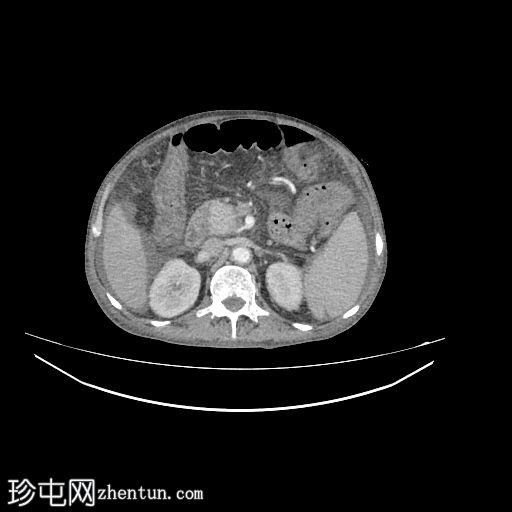

轴位

平扫

肝脏轻度肿大,未见肝内胆管扩张。近端和中段胆总管扩张至8 mm,远端突然中断,门周脂肪间隙增厚。

胰腺轻度肿大,胰周脂肪间隙增厚,符合急性胰腺炎表现。

胃大弯壁内可见一囊肿,大小为7.6 × 4.3 cm,囊壁厚度为2.5 mm,可见强化。脾门处可见另一囊肿,大小为 4.8 × 3.0 cm。

盲肠和升结肠壁水肿增厚,可能为反应性改变。

腹主动脉、脾动脉、腹腔干和肠系膜上动脉可见动脉粥样硬化改变。

中度腹水。双侧轻度胸腔积液(右侧较左侧多)。